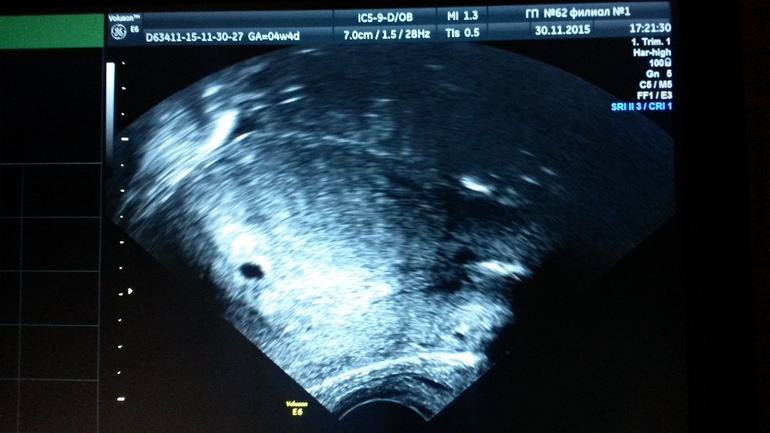

Ксюш, можешь сходить, вреда от узи нет, я как врач говорю. Это только звук. Сделают внутр Доплер (презик на узи не забудь). Определят плодное яичко, маточную и успокоишься, будешь растить. Я Горошика пошла смотреть в 4 нед и 4 дня, определили ПЯ, Б мат и точечку 2 мм, это был Горошик. Все, теперь в 7 нед идем показываться и прослушиваться. Сделаем фото на память, обязательно.

Вот мы в 4 нед